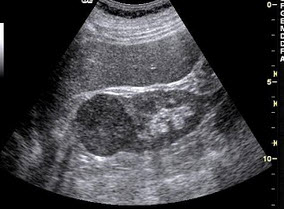

52、单项选择题

女性,29岁,停经28周,产前超声检查如图,最可能的诊断为()

A.胎儿畸形,脑积水

B.胎儿畸形,腹壁裂

C.胎儿畸形,室间隔缺损

D.胎儿畸形,无脑儿

E.胎儿畸形,露脑畸形